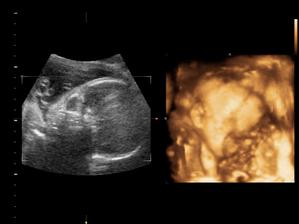

Nas anjelik Alex

Zatial este schovany v brusku ale uz coskoro sa z neho potesime aj nazivo 🙂) Lubime nasho Alexa uz od sameho zaciatku 🙂